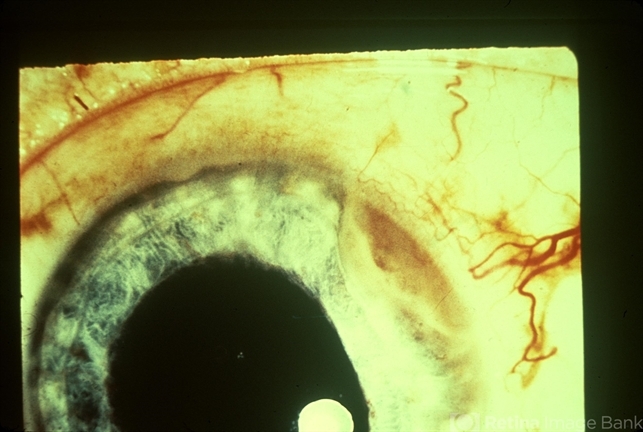

- ciliary body tumor, feeder vessel

- External photo of ciliary body tumor with dilated feeder vessel.